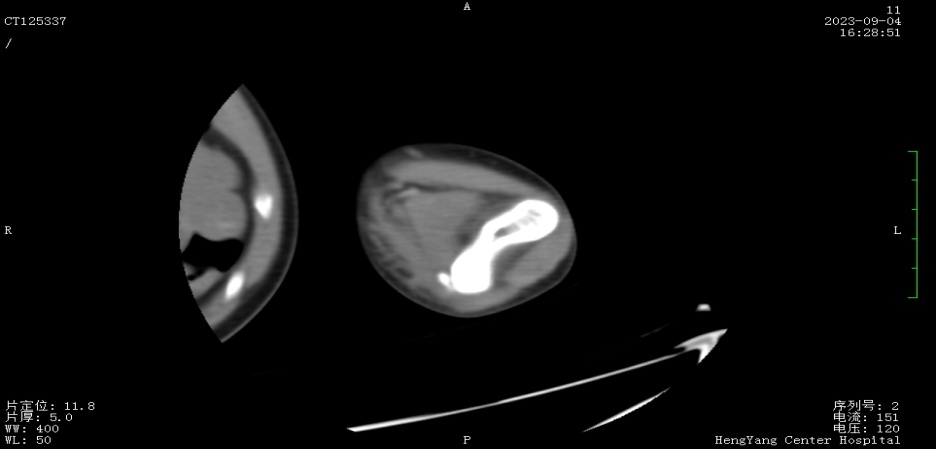

接診后,醫(yī)師發(fā)現(xiàn)小莫同學(xué)的左肘關(guān)節(jié)自然狀態(tài)下僅能伸展至約115°,并伴有習(xí)慣性屈肘。經(jīng)與骨科醫(yī)生溝通并閱片后,考慮骨化肌炎,針對(duì)這種情況,一般采取手法松解關(guān)節(jié)和關(guān)節(jié)功能鍛煉相結(jié)合的治療方案。但此方案常用于成人患者的關(guān)節(jié)粘連傳統(tǒng)松解術(shù)和關(guān)節(jié)松動(dòng)訓(xùn)練,對(duì)于兒童來說刺激強(qiáng)度太大,且因兒童骨骼及關(guān)節(jié)較成人脆弱,無法保證治療的連續(xù)性及安全性,若一味采取輕柔手法,不僅治療時(shí)間長、見效慢,還可能加重后續(xù)治療難度。

首次治療結(jié)束后,小莫同學(xué)的左肘關(guān)節(jié)即可伸展至145°。9月19日,小莫同學(xué)已結(jié)束第一階段共14次治療,他的左肘關(guān)節(jié)就可以自然伸展至170°,可滿足上肢基本功能需求。